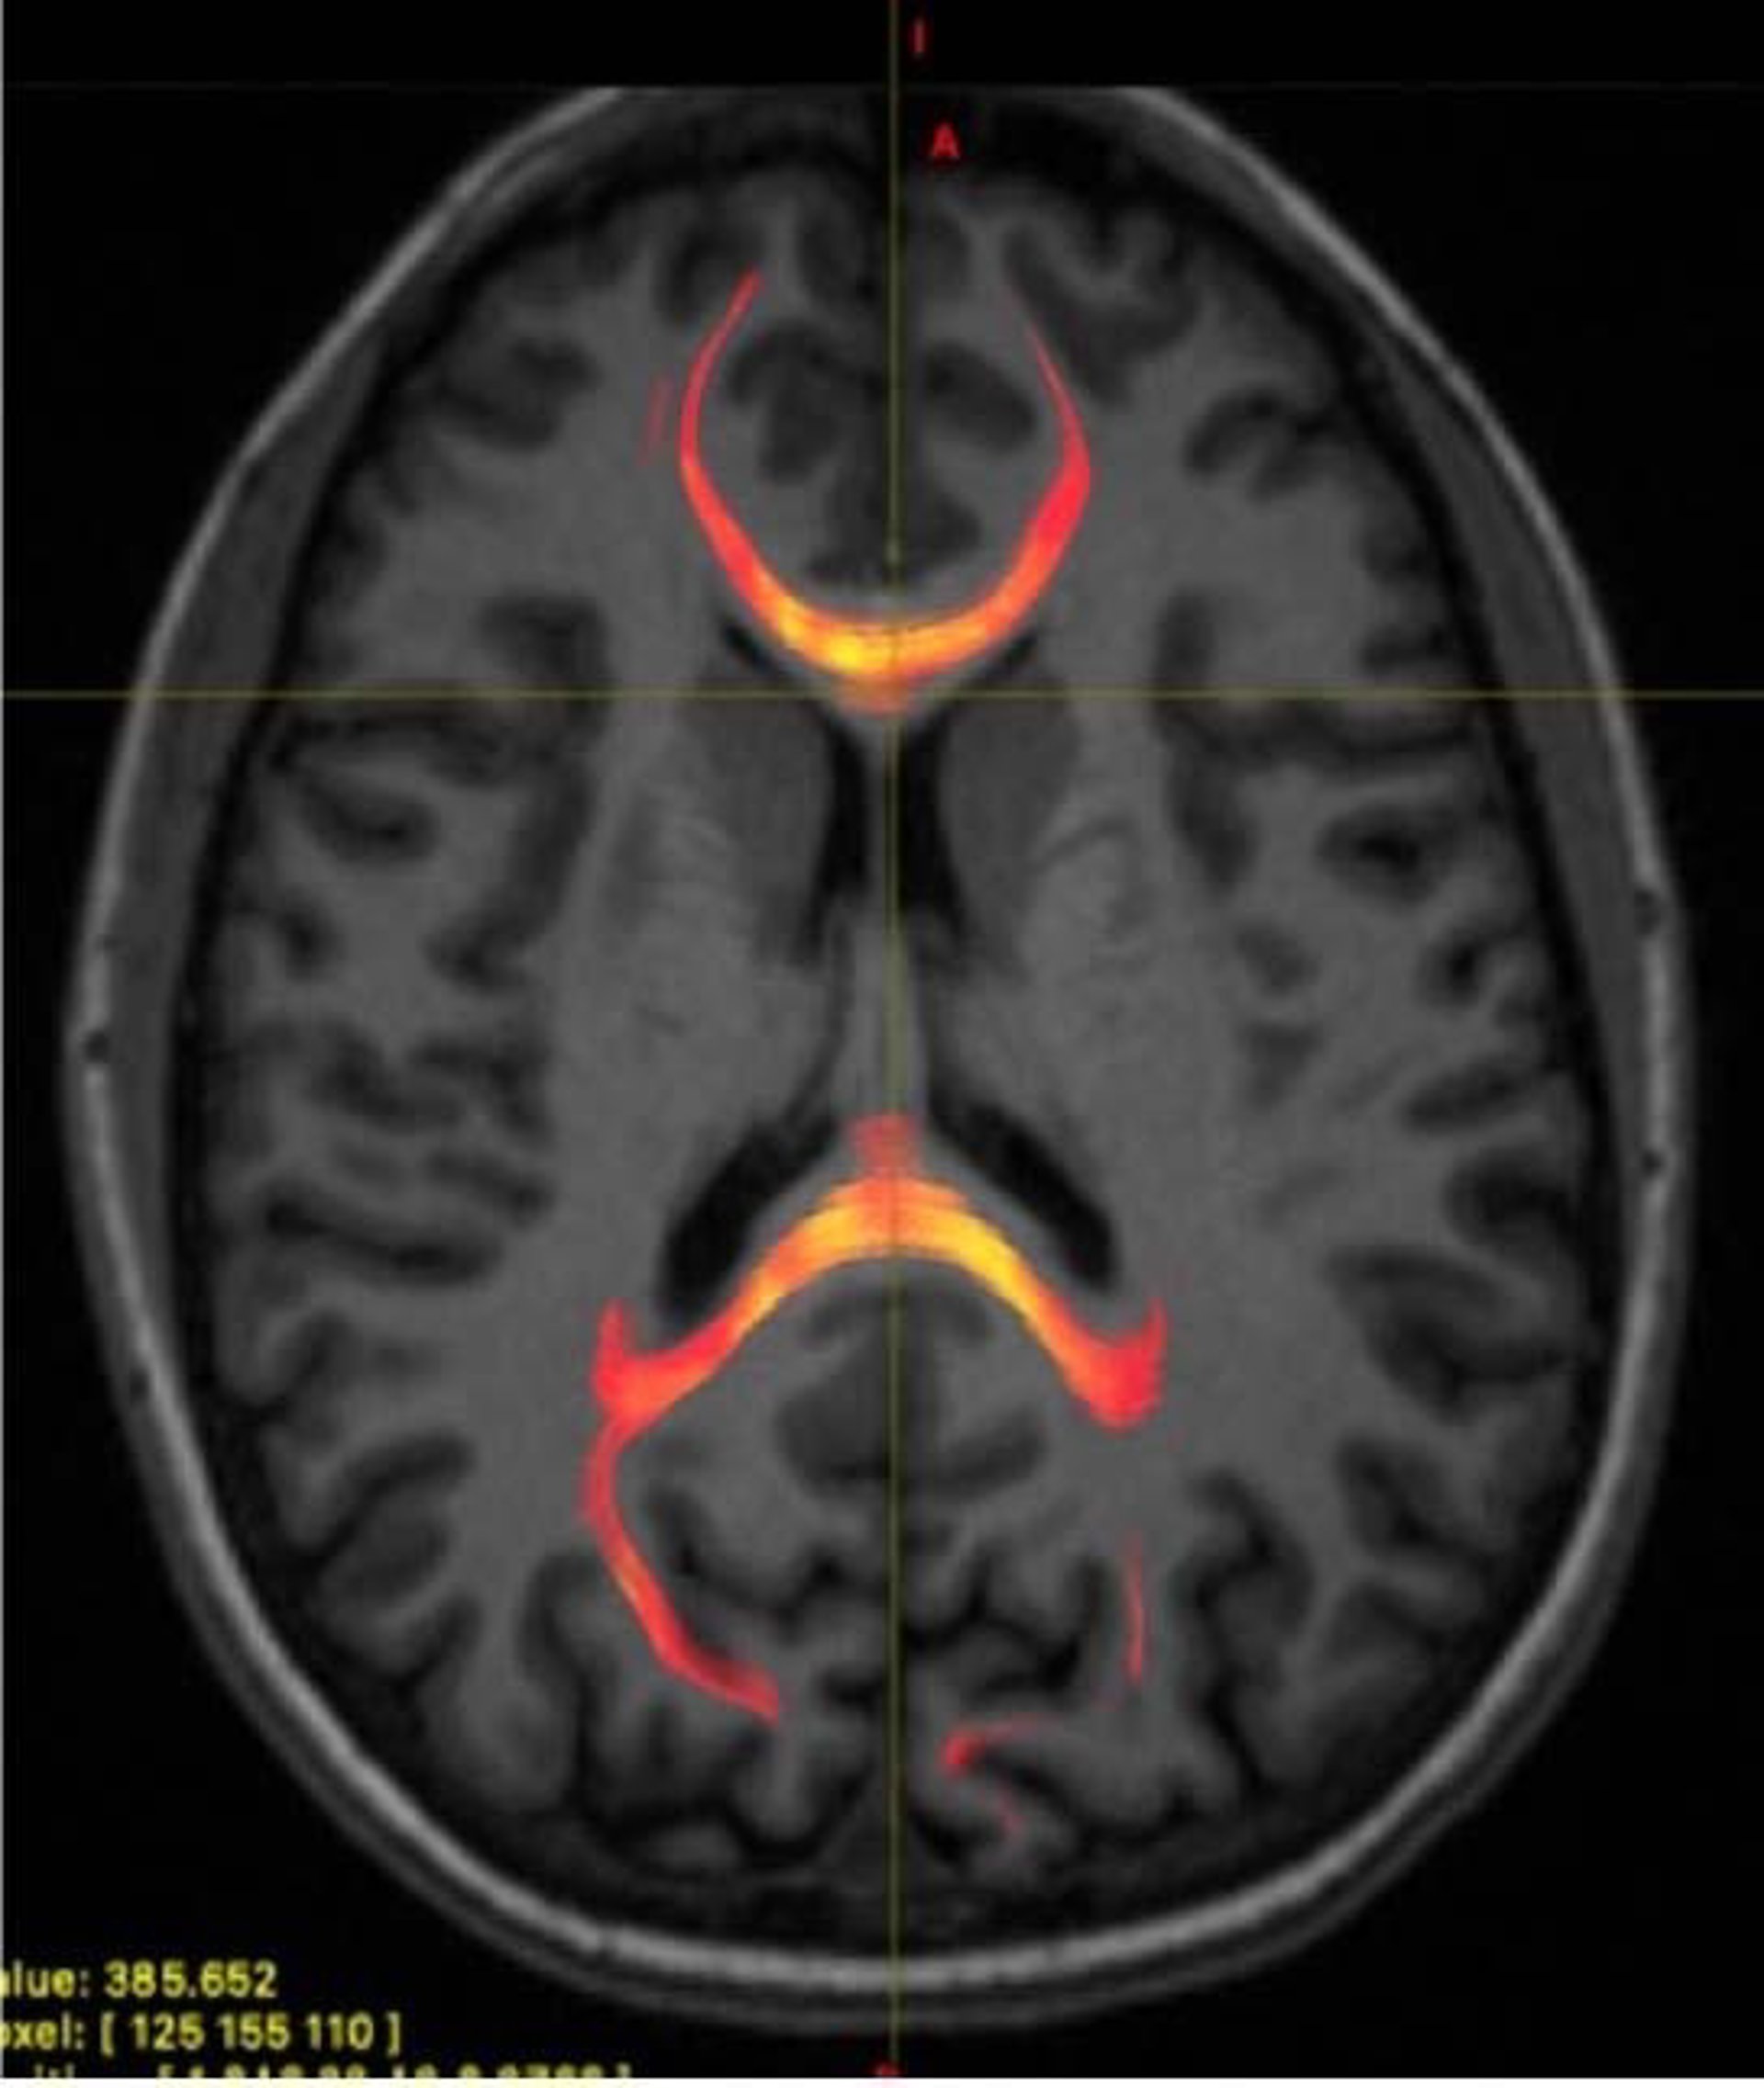

Archivo - Imagen de RMN de un paciente con lesión cerebral traumática leve que muestra tractografía de fibra callosa del cuerpo

Archivo - Imagen de RMN de un paciente con lesión cerebral traumática leve que muestra tractografía de fibra callosa del cuerpo - RSNA - Archivo